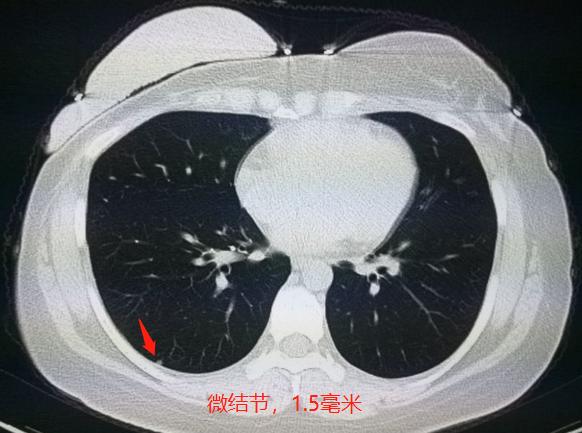

在术后一整年的时候,复查胸部CT发现右下肺微结节,不足2毫米:

1.5毫米的微结节,会不会是转移呢?会不会是新发的肺癌呢?会不会只是小淋巴结呢?

不好说!太小了,没有特征性,也无法通过穿刺确诊(体积太小),化验肿瘤标志物也正常。